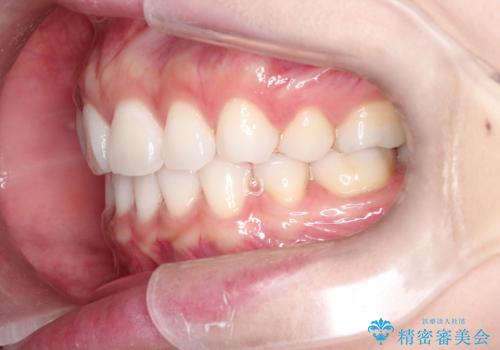

口が閉じにくい 口ゴボの抜歯矯正による改善

- 20代女性

- 口が閉じずらく、口元が出ていることを主訴に来院されました。

上下左右の歯を1本ずつ抜歯して、そのスペースを利用して口元を引っ込める計画としました。

口元を下げて口唇を閉じやすくする場合、抜歯矯正をお勧めさせていただくことが多いです。